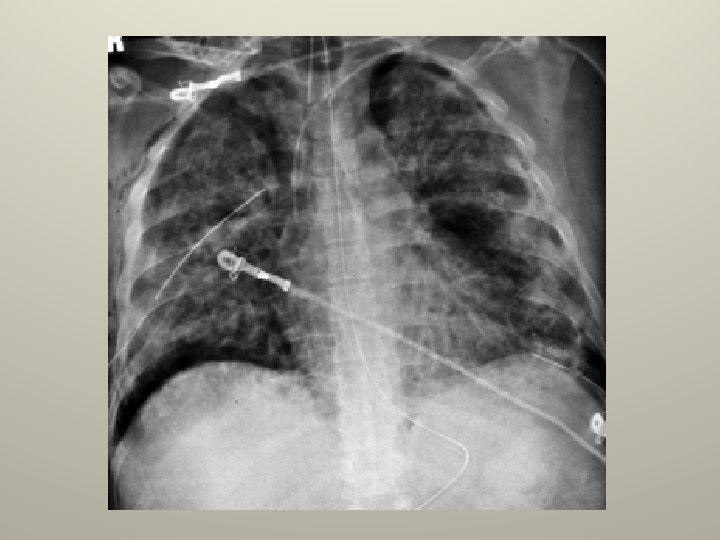

SINDROME DE DISTRESS RESPIRATORIO AGUDO Paradigma de la IR aguda

SDRA www. reeme. arizona. edu

Definición Injuria pulmonar aguda SDRA Pa. O 2/Fi. O 2 < 300 < 200 Infiltrados Bilaterales si si PCP < 18 mm. Hg

Causas de SDRA • • • Sepsis Aspiración Neumonía Intoxicación Ahogamiento Inhalación de tóxicos Quemaduras extensas Contusión pulmonar Tranfusiones • • • Embolía grasa Obstrucción vía aérea sup. Transplante Drogas Revascularización miocardica Pancreatitis Neumonía eosinofila BOOP TBC miliar

Fisiopatología del SDRA Injuria pulmonar o extrapulmonar Daño epitelial Proliferación celular Shunt “celular” Daño endotelial Edema Shunt “líquido” Vasoconstricción. HTp CRF y distensibilidad Hipoxemia Pérdida de vasoconstricción hipóxica

Mecanismos de hipoxemia • Pulmonares: Shunt: Edema, colapso, consolidación V/Q: Hipoventilación, pérdida de la vasoconstricción hipóxica, trombosis, sobredistensión alveolar, remodelación pulmonar tardia • Extrapulmonares: SVO 2 baja. Cortocircuito extrapulmonar